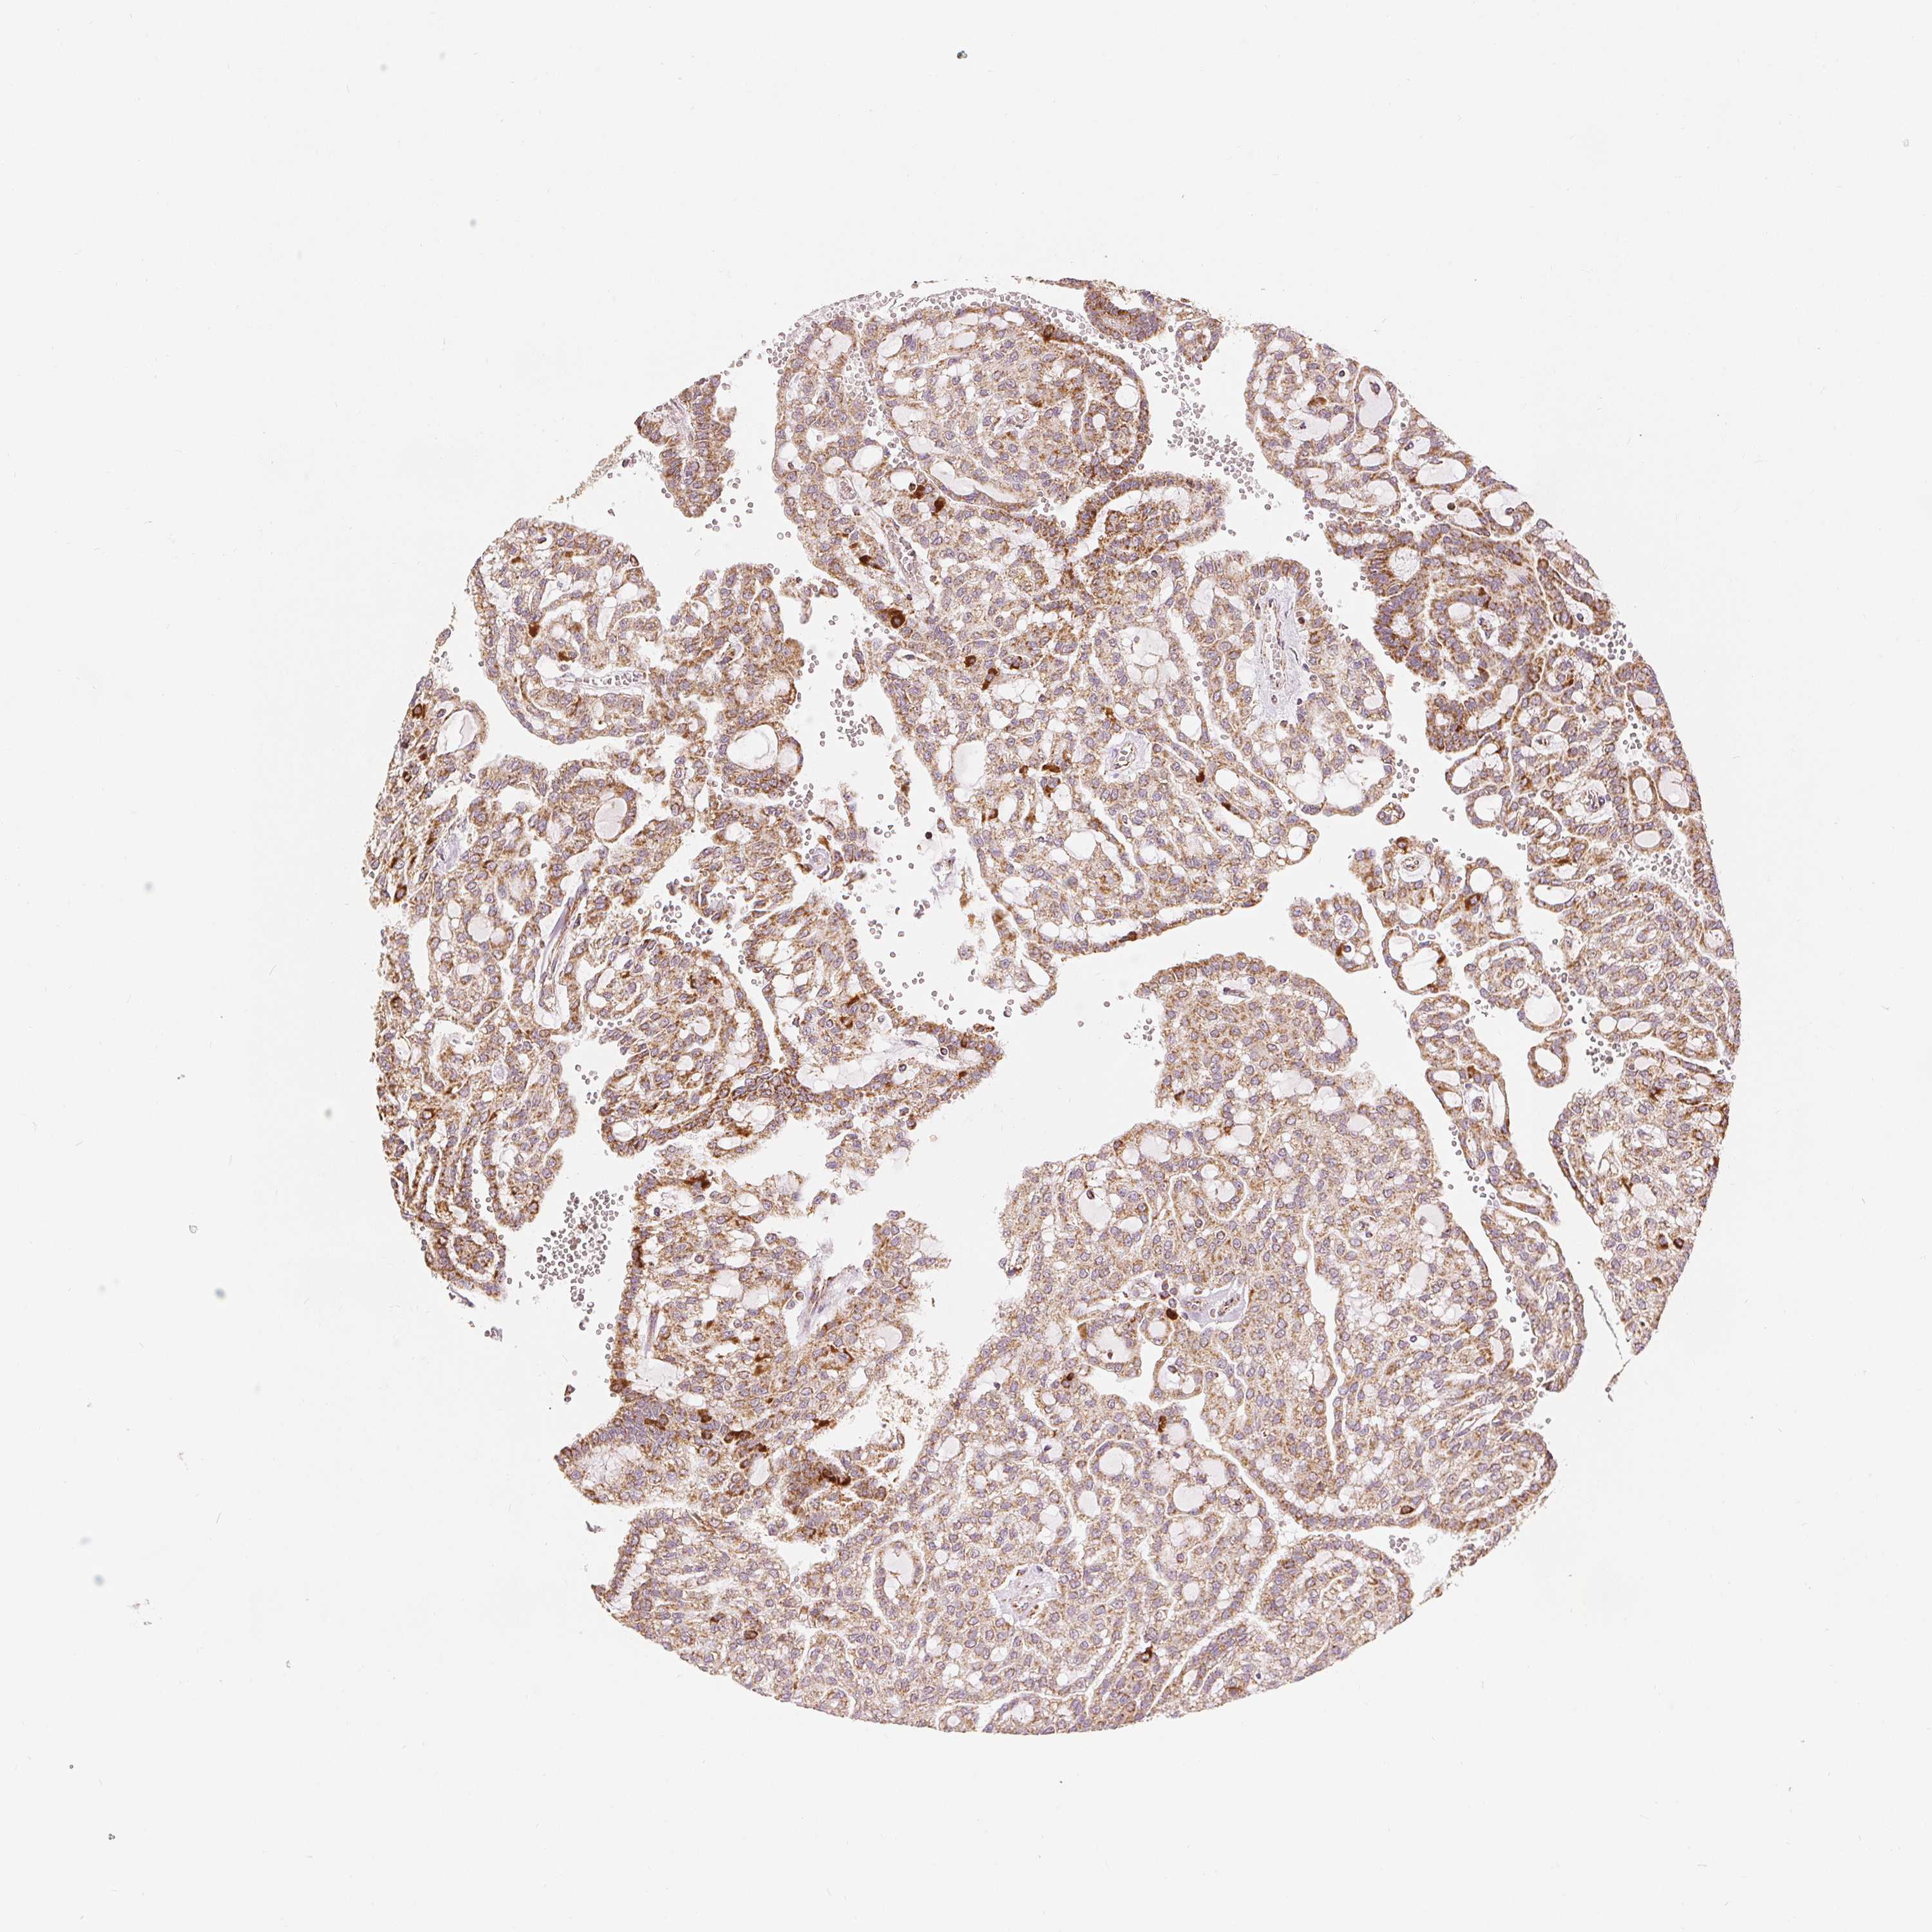

KIDNEY RENAL PAPILLARY CELL CARCINOMA (TCGA) - Interactive survival scatter ploti

The Survival Scatter plot shows the clinical status (i.e. dead or alive) for all individuals in the patient cohort, based on the same data that underlies the corresponding Kaplan-Meier plots. Patients that are alive at last time for follow-up are shown in blue and patients who have died during the study are shown in red.

The x-axis shows the expression levels (FPKM) of the investigated gene in the tumor tissue at the time of diagnosis. The y-axis shows the follow-up time after diagnosis (years). Both axes are complimented with kernel density curves demonstrating the data density over the axes. The top density plot shows the expression levels (FPKM) distribution among dead (red) and alive patients (blue). The right density plot shows the data density of the survived years of dead patients with high and low expression levels respectively, stratified using the cutoff indicated by the vertical dashed line through the Survival Scatter plot. This cutoff is automatically defined based on the FPKM cutoff that minimizes the p-score. The cutoff can be changed by dragging the vertical line or by entering a cutoff value in the square labeled "Current cut-off".

Under the Survival Scatter plot the p-score landscape (black curve; left axis) is shown together with dead median separation (red curve; right axis). Dead median separation is the difference in median mRNA expression between patients who have died with high and low expression, respectively. It is calculated as follows: median FPKM expression of dead patients with high expression - median FPKM expression of dead patients with low expression. This is intended to aid the user in visually exploring custom cutoffs and the associated p-scores and dead median separation.

Individual patient data is displayed and can be filtered by clicking on one or more of the category buttons on the top of the page. Categories describing expression level and patient information include: high, low, alive, dead, female, male and tumor stages. The scale of the x-axis can be toggled between linear and log-scale by clicking on the "x log" button. Mouse-over function shows TCGA ID, patient information and mRNA expression (FPKM) for each patient.